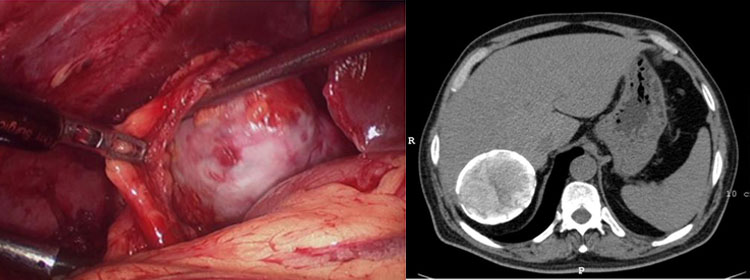

Hydatid cysts of the liver

Common liver affliction in India, hydatid cyst is a parasitic disease caused by a tape worm carried by domestic dogs.These cysts can occur in patients who consume foods contaminated by faeces of dogs affected by tapeworms.

These foods are essentially green leafy vegetables not washed properly. Unlike simple cysts these are active cysts and keep growing. Majority of these cysts will require surgical treatment either by laparoscopic or open methods.

The treatment for these cysts is either a marsupialisation or a cysto-pericystectomy by laparoscopy. Spillage of cyst contents can sometimes cause anaphylactic reaction and occasionally dissemination of hydatid disease. These patients also require long term medication with albendazole.